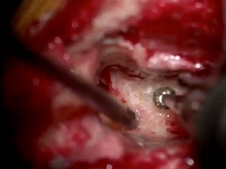

Retrosigmoid Approach for Resection of Vestibular Schwannoma with Hearing Preservation

- Date : 01/01/2020